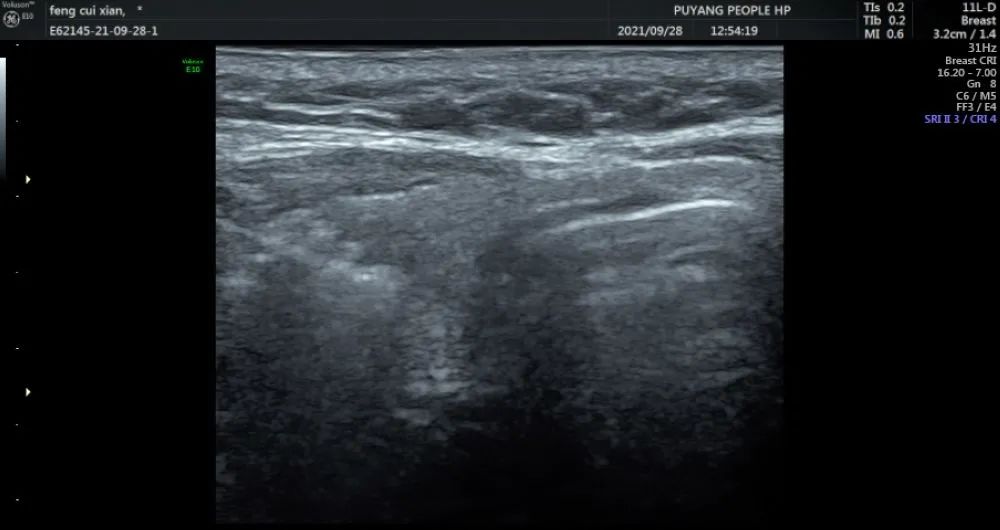

通过术前评估,细致准备,在实时超声的引导下,射频消融针精准地进入恶性病灶内,仅用时3分钟左右,消融范围就完全覆盖病灶并局部扩大消融范围。

超声引导下甲状腺结节射频消融术是一种比较新的技术,它是使用高频电流在结节内产生局部的温和热量,这种热量通过电极针传导,来损毁病灶,治疗后结节发生变性坏死灭活,从而实现有效治疗,这样将出血量和瘀血降到最低。与传统外科手术相比,射频消融治疗的优势是定位准确、无需全麻、创伤微小等特点,从而实现无痕治疗,让健康与美丽同行。